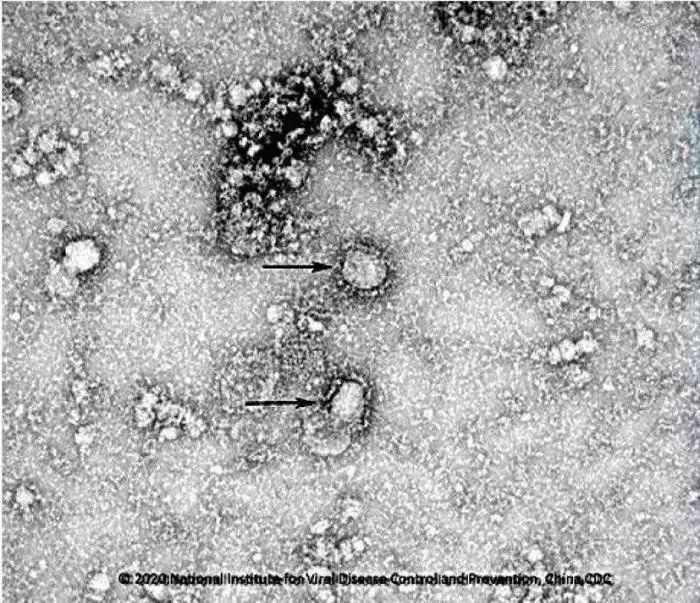

資料圖:新型冠狀病毒武漢株01 圖片來源:中國疾控中心網(wǎng)